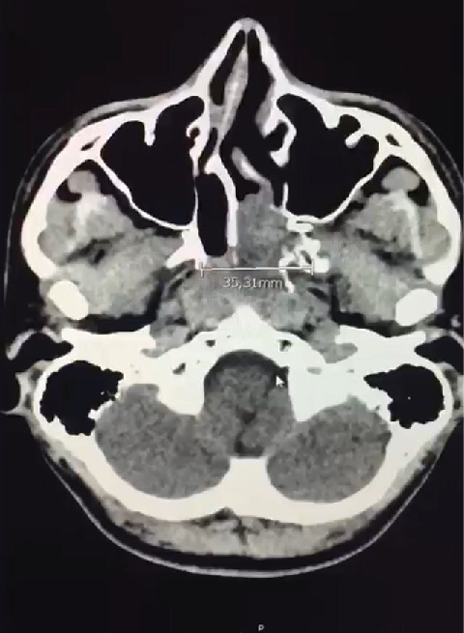

Paciente del género masculino de 19 años de edad sin antecedentes de importancia, quien consulta por cuadro clínico de 7 días de evolución caracterizado por cefalea hemicraneada izquierda no pulsátil sin irradiación asociado a otalgia izquierda y sensación de opresión ocular izquierda. Quien previamente había consultado extra-institucionalmente con manejo analgésico sin mejoría, consulta nuevamente por aumento del dolor clasificado 10/10 en la escala análoga del dolor, sin síntomas visuales, sin sangrado nasal y sin alteraciones neurológicas. A la revisión por sistema informa episodios de alteración del olfato desde los 7 años de edad y único episodio de epistaxis en fosa nasal izquierda auto limitado a los 16 años de edad. Como único antecedente patológicos rinitis alérgica intermitente y antecedente toxico una aparente exposición al polvo de madera; al examen físico la rinoscopia anterior mostró hipertrofia de cornetes bilateral y mucosa pálida, sin masas en región anterior. Se solicito tomografía axial computarizada cerebral con hallazgos de masa de densidad de tejidos blandos que ocupa la coana izquierda, infiltra parcialmente la región posterior de la fosa nasal de este lado, erosiona la apófisis pterigoides. Tiene diámetros aproximados de 47 x 34 x 35 mm en los ejes craneocaudal, rostro dorsal y axial respectivamente (Figura 1).